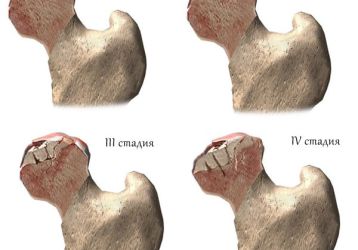

Коксартроз тазобедренного сустава 4-й степени: лечение и операция

Лечение коксартроза тазобедренного сустава 4-й степени невозможно без операции. Симптомы, хирургические техники и перспективы восстановления.

Артроз — это одно из самых опасных поражений сочленений, которое без надлежащей терапии может привести к деформации, а также дисфункции сочленений. Болезнь имеет дегенеративно-дистрофический характер. В основном поражается именно хрящевая ткань, которая отвечает за амортизационные свойства суставов.

Характеризуется патология сильными болевыми ощущениями, ограничением подвижности человека, а также изменением самого сочленения (часто не обратимым). Существуют такие виды заболевания: